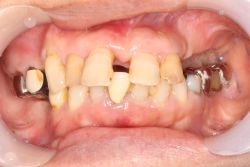

中間欠損 60代 女性中間欠損 MTC 2025.09.29 治療前 治療後 治療名称フレアアウト症例を単独冠と上下のMTコネクターで補綴し、機能と審美の回復を図った症例 アイヒナー分類B4期間–費用–治療内容–治療に伴うリスク– 30代 女性中間欠損(1・2本) MTC 前の記事 男性両側遊離端 MTC 次の記事